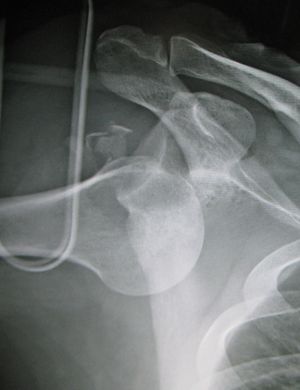

Inferior shoulder dislocation

- Also known as "Luxatio Erecta" due to the presentation of arm held in full abduction

- Plain film X-ray in at least 2 views

- Post-reduction X-ray